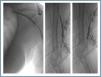

First, using ultrasound monitorisation, the access is threaded in the opposite direction from the arterial anastomosis. A guide wire and catheter is used to clear the obstructed segment to connect with the venous area free from thrombus. For PTFE grafts, this area is generally distal to the venous anastomosis. A safety wire is placed and we begin to aspirate thrombi with a large 7 to 9 French catheter (figures 1 and 2). Once the segment is free from thrombi, the catheter is threaded toward the arterial anastomosis and the same operation is repeated. When the access is free from thrombi, we inflate the underlying stenotic areas responsible for the thrombosis with an angioplasty balloon (figures 3 and 4). Medication during the procedure consists of midazolam as a sedative, an antibiotic (third-generation cephalosporin) and a heparin bolus with 3000-5000 IU of sodium heparin. If the patient needs dialysis immediately, the catheter introducers are left in and dialysis is performed using them. LMWH is recommended on non-dialysis days.

In 81 cases (80.2%) the thrombectomy was accompanied by angioplasty of the underlying lesion or lesions; in 14 cases (13.9%), in addition to thrombectomy and angioplasty, one or more stents was implanted; and in six cases (5.9%) thrombectomy was performed alone.

Figure 3.